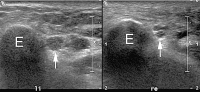

Abbildung 5: Sonographischer Querschnitt durch den Sulcus nervi ulnaris bei einem Patienten mit posttraumatischer Ulnarisparese. Im Seitenvergleich ist der Nervus ulnaris (Pfeil) der betroffenen linken Seite deutlich ödematös aufgetrieben, bei Verlust der faszikulären Gliederung. E: Epicondylus medialis numeri.

Abbildung 11a-b: (a) Sonographischer Querschnitt durch den Nervus cutaneus femoris lateralis (Pfeilspitzen) im Seitenvergleich. Der Nerv der linken Seite ist massiv ödematös verdickt. (b) Sonographisch gezielte Cortison-Instillation an den Nerv (lange Pfeile). Kurzer Pfeil = Nadel; Pfeilspitzen = verteiltes Cortison.